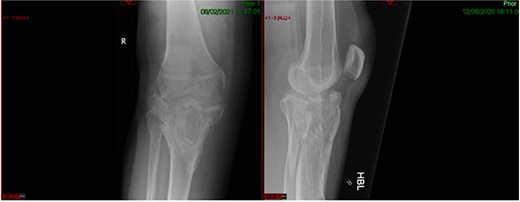

A 68-year-old gentleman who was diagnosed with a Schatzker type VI fracture having fallen 3 m from a ladder (Figs 1 and 2). The injury was closed and neurovascularly intact. The patient was monitored for signs of compartment syndrome. He rapidly developed significant fracture blisters that persisted for over 2 weeks despite regular dressing care. He was deemed too high risk for acute operative intervention because of a high risk of wound complications. Following a multidisciplinary team discussion, he was managed in a cast then a knee brace, mobilising non weight bearing for 12 weeks, at which point the fracture was seen to be healing in a valgus malalignment. The patient was allowed to partially weight bear and received physiotherapy. He was reviewed regularly until fracture had united (Fig. 3). At 8 months post-injury, the patient underwent total knee arthroplasty utilizing a Depuy Synthes (Warsaw, In) PFC Sigma TC3 tibial metaphyseal sleeve and stem, and femoral component without sleeve or stem (Fig. 4). The patient was reviewed post-operatively in clinic at 6 months, the wound had fully healed and the range of motion was 0°–120°. The patient’s pain was significantly reduced, and they were independently mobile. They were kept under annual review and seen at 5 years post-operatively with an Oxford Knee score of 35; the patient used no walking aids and was pain free at rest or during normal walking, with the radiograph demonstrating good osseointegration. The latest follow-up at 8 years revealed no radiographical change in implant (Fig. 5).